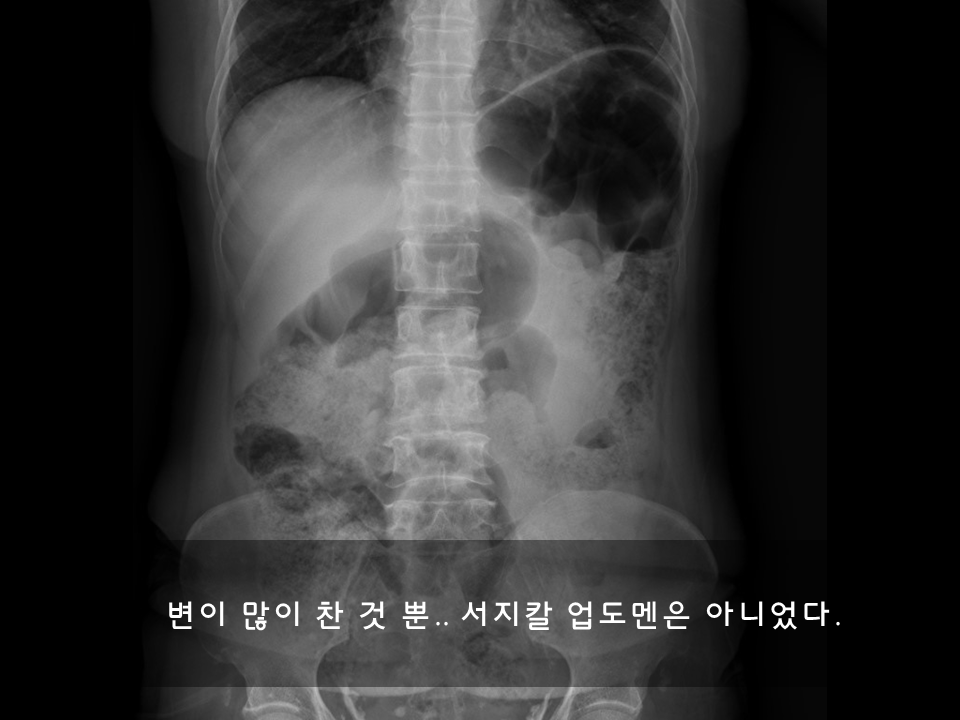

굵은 금목걸이에 있음직하게 치장을 한 탄탄한 체구의 아저씨는 배가 아프다며 진찰을 원했다. 신체검진을 해보니 서지컬 업도멘surgical abdomen(수술이 필요할 만한 복통)은 아니었다. 응급실에서는 복통이 있더라도 서지컬 업도멘surgical abdomen이 아니면 중요도가 뚝 떨어진다.

여유 있게 환자의 병력을 정리하며 약을 처방하고 보내려고 했다. 그런데 굳이 정밀 검사를 원하는 것이다. “응급실은 진찰료며 검사료가 일반병원 보다 훨씬 비쌉니다. 응급상황이 아닌데 굳이 여기서 검사하실 이유가 없습니다.”하며 만류했지만 막무가내였다. CT촬영은 의미가 없을 듯 하여 간단한 엑스레이 검사와 혈액검사를 했고 특별한 이상소견은 없어서 약을 처방해서 퇴원처리를 했다.